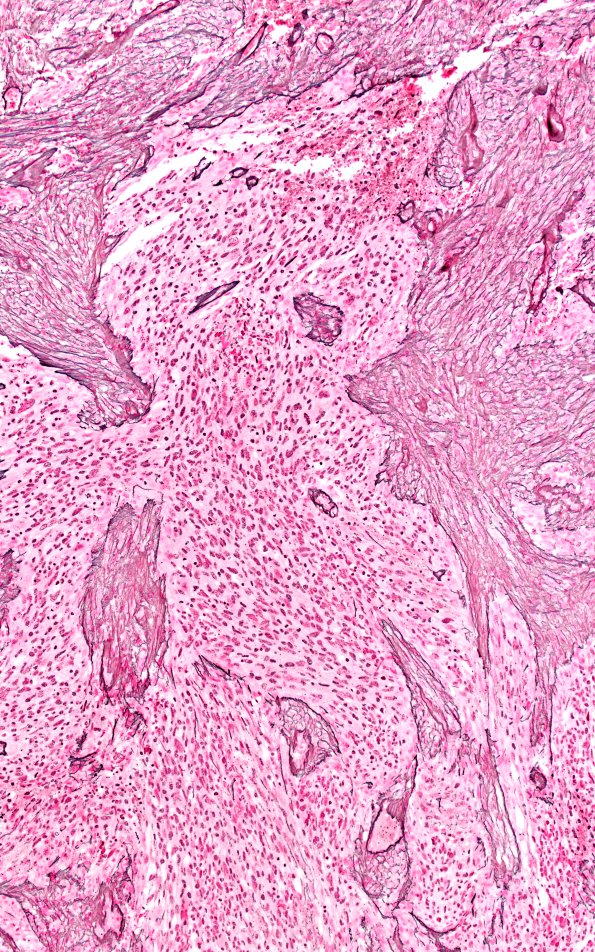

23A9 Gliosarcoma (Case 23) Retic 10X A

Reticulin stain of area 23A7.